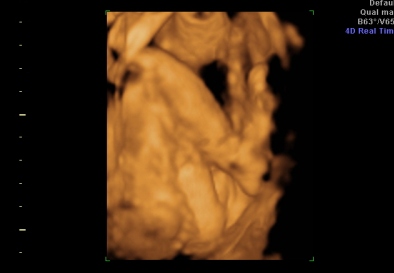

Na hát megvolt a 4D. Jó sokat időztünk ott, Mártika annyira kedves volt kaptam csokit ,colát, sétáltam mert a drágánk a feje előtt tartotta a két kezet plusz az egyik lábfejét, és belebújva a méhlepénybe. Szóval alig se nagyon látszott valami kb 1órát időztünk. HÁt ezért szeretek én a Genesisbe menni mert annyira lelkiismeretesek.

Hoztam pár képet

pofi

Kép

keze

tuti lányos